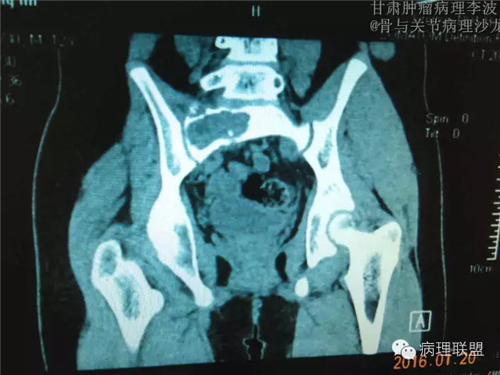

M/14 骶骨骨肉瘤-张惠箴讲解

病例由甘肃肿瘤病理 李波 提供,致谢。